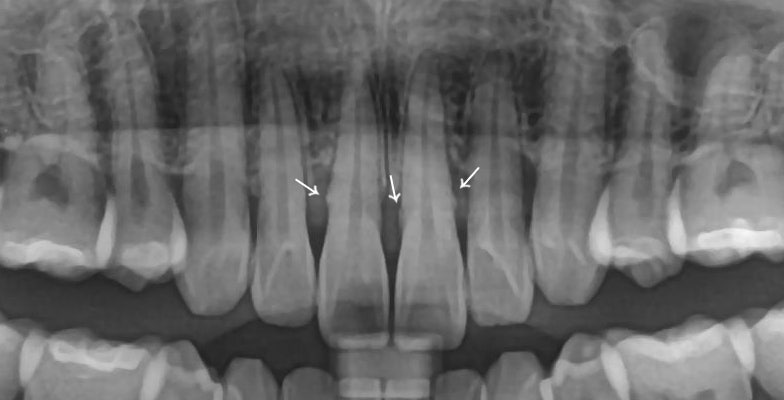

파노라마 엑스레이에서 보이는 치석(울퉁불퉁)

엑스레이 사진에서 이렇게 울퉁불퉁 보일정도면

상당히 치석이 많이 붙었다고 볼 수 있습니다.

그걸 마취 하고나서 깨끗이 긁어내요

치석 제거 완.

그러면 이렇게 매~끈한 뿌리를 가질 수 있습니다.

만약 치석을 제거하지 않고

레진을 떼운다면 어떻게 됐을까요?

치석이 더 잘 쌓이게 되는 건 물론이고

치석 위에 레진을 쳐발쳐발하게 되면

당연히 레진과 치아 사이 접착이 실패하고

잇몸은 계속해서 안좋아지겠죠...

이렇게 예상되는 문제를

미리 제거하고 레진을 해야합니다.